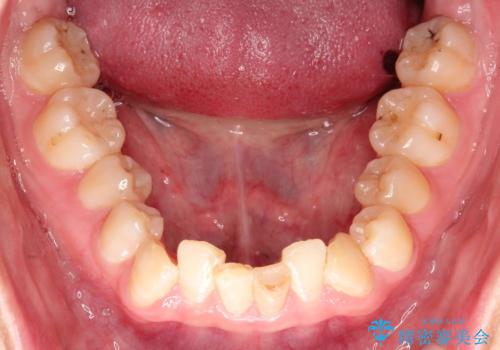

ハーフリンガル ワイヤー矯正による非抜歯・過蓋咬合の治療

- 非抜歯、大臼歯遠心移動による臼歯関係の是正・過蓋の改善をハーフリンガル・ワイヤー矯正にて計画した。

現在過蓋咬合の非抜歯治療はマウスピースで行うのが第1選択といっても過言ではありません。

しかし、諸々の理由でマウスピース矯正をおこなえない場合、本例のようにワイヤーを用いて治療することも可能ですが、そもそも装置が歯につかないため、非常に大変な労力を費やすことになります。